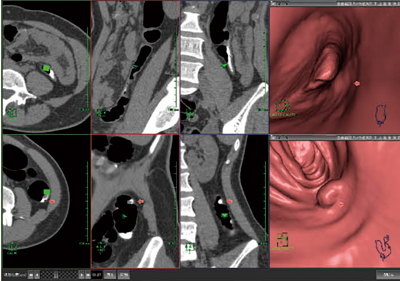

AZE VirtualPlaceの最新大腸解析ソフトウェアは,画像読み込みを行うだけで,大腸のフライスルー検索や展開画像解析を自動的に行うことが可能である。2方向(仰臥位・腹臥位など)での解析にも対応し(図1),より正確な診断を簡単に行うことができる。デジタルクレンジング技術も搭載しているため,前処理を行うことにより,残渣領域の診断に使用可能である。解析レイアウトもユーザーに合わせて切り替えて使用することにより,大腸のスクリーニング検査などをより迅速に解析・診断することが可能となる。

図1 仰臥位・腹臥位の2方向解析